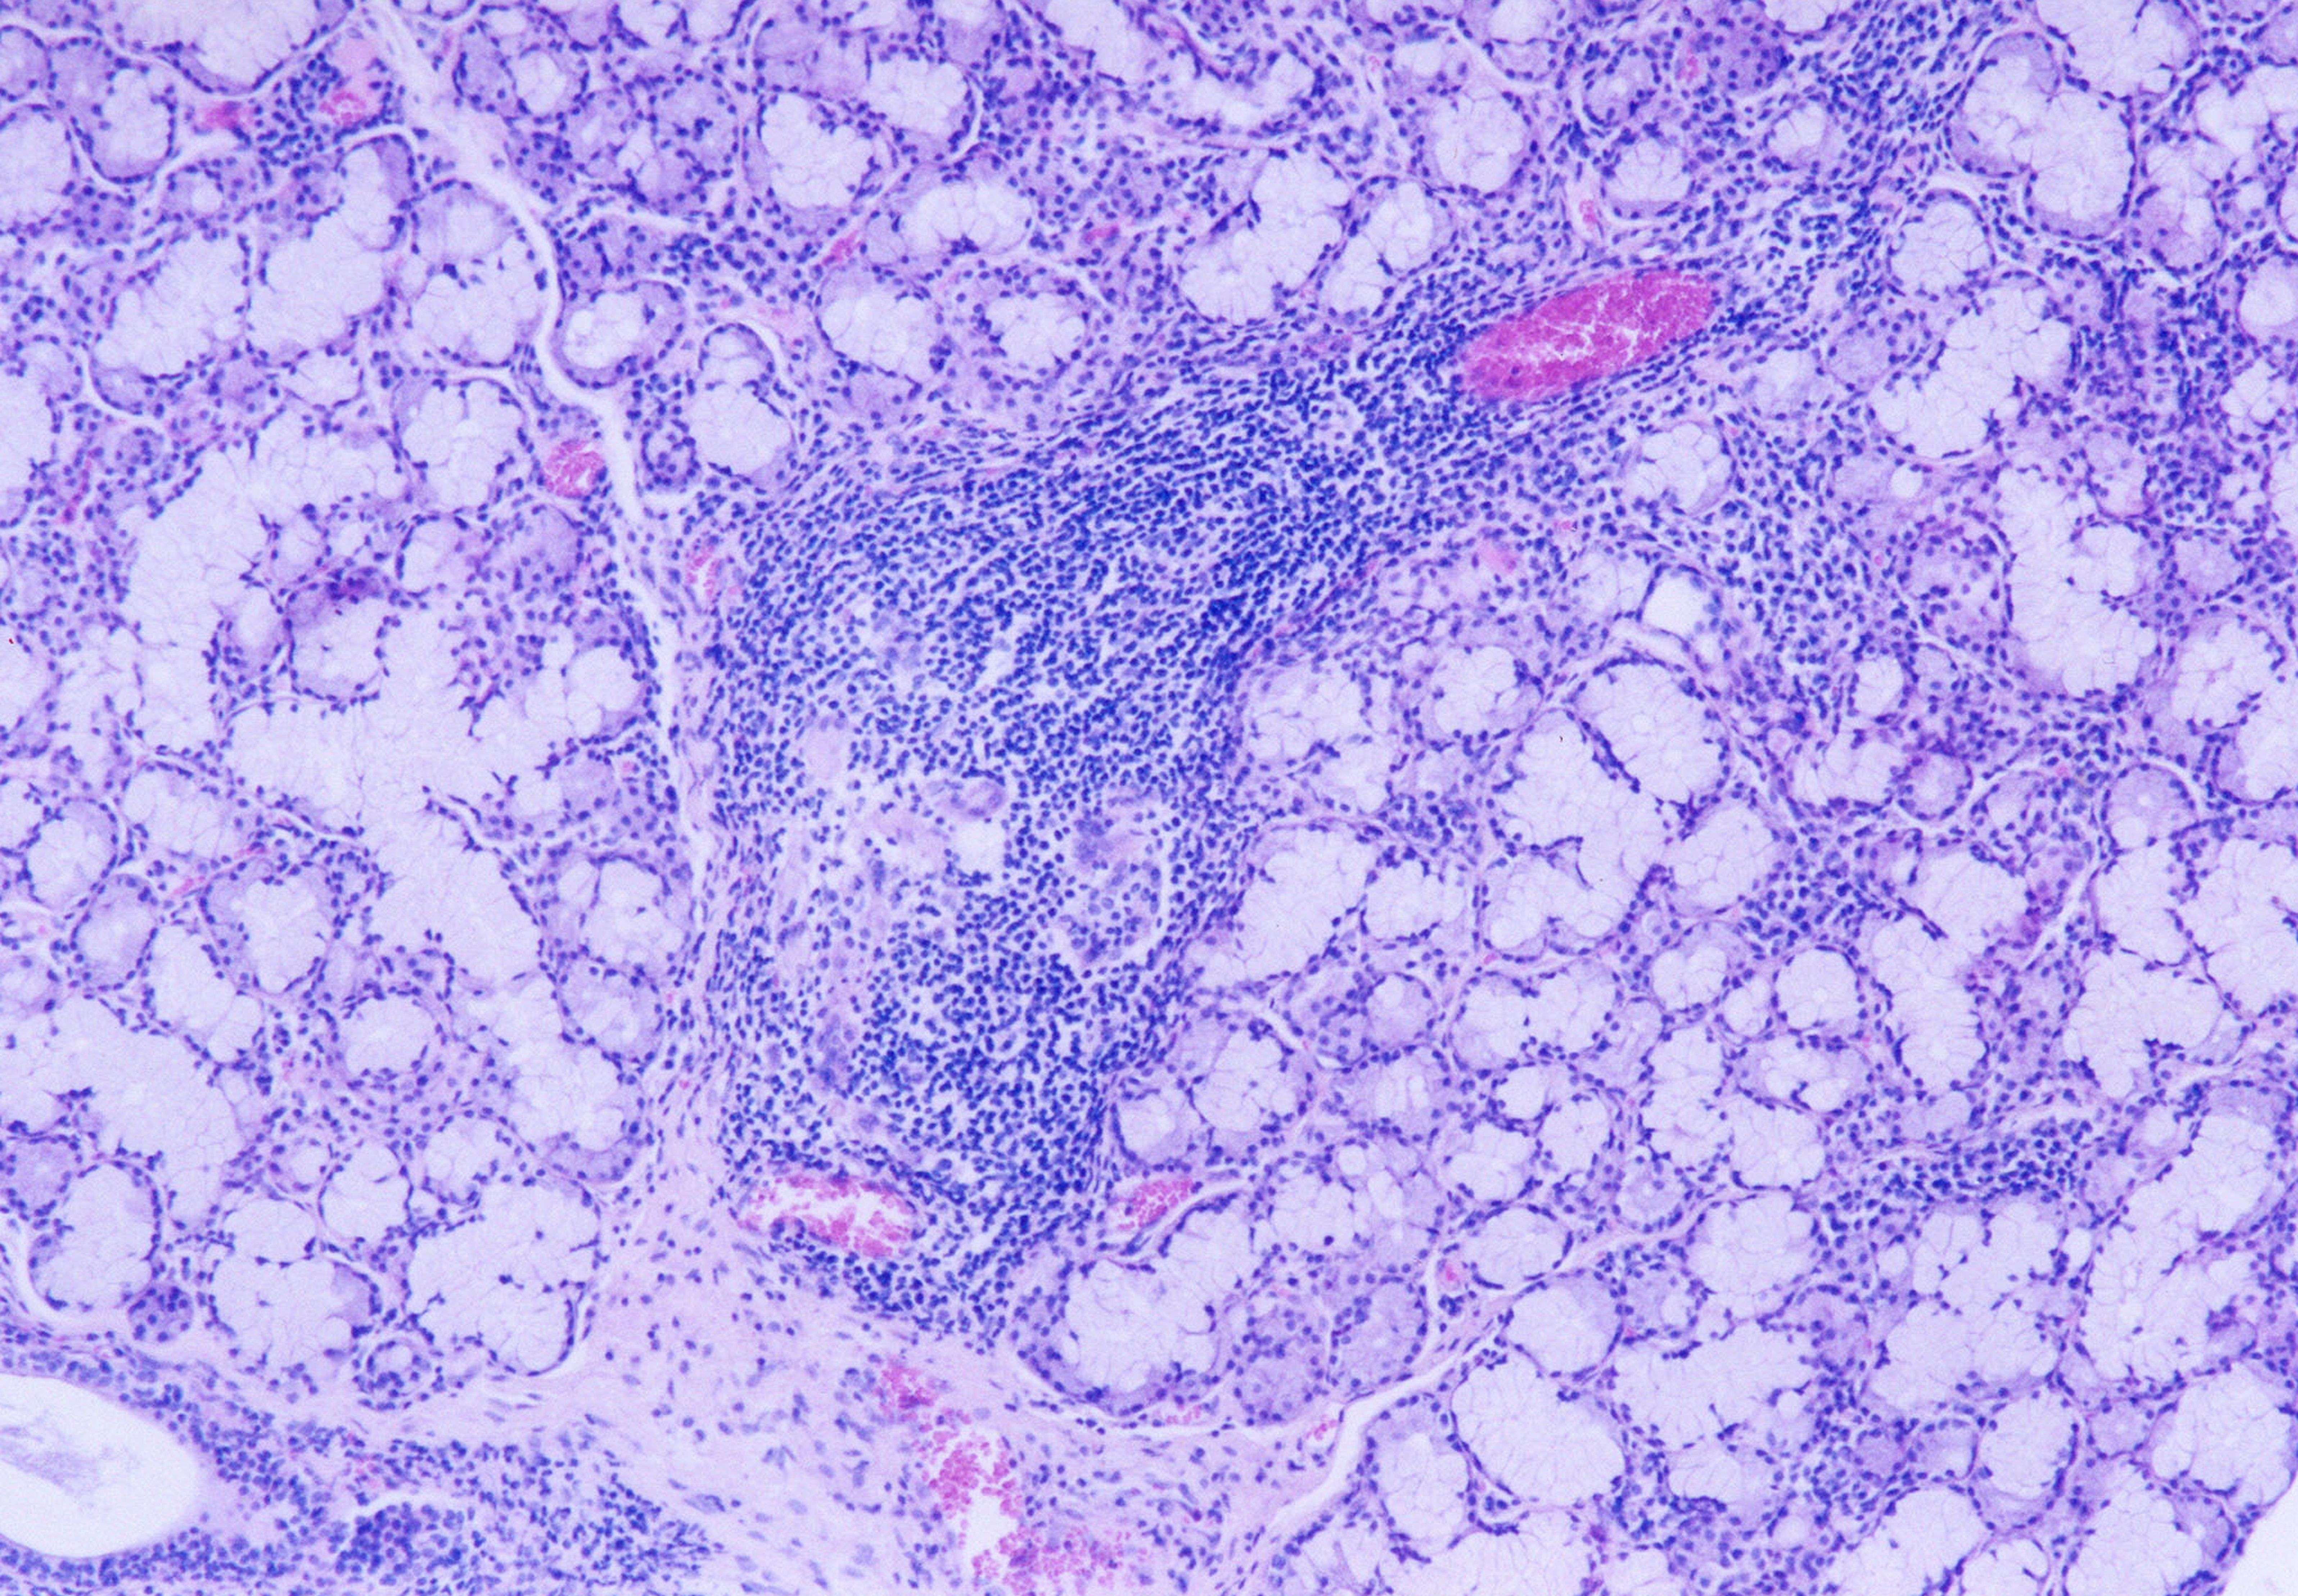

The laboratory studies showed hemoglobin, 13.1g/dL; white blood cells, 5140/mm3; and platelets, 165,000/mm3. A serum sample was tested for the presence of antinuclear antibodies (ANA) (indirect immunofluorescence using HEp-2 cell lines), anti-SSA and anti-SSB antibodies (enzyme-linked immunosorbent assay), and rheumatoid factor (nephelometric method). The results demonstrated a dotted pattern for the ANA test (1:320), positive results for anti-SSA test and negative findings for anti-SSB, and the rheumatoid factor was elevated at 80.5 µL/mL (normal, -20). Minor salivary gland biopsy revealed a focal periductal lymphocytic infiltrate, which, taken together with the other diagnostic test findings, confirmed the SS diagnosis (Figure 8 through Figure 11).

Fig 8. Histopathologic appearance of minor salivary gland biopsy (hematoxylin–eosin). Lower-power magnification showing focal periductal lymphocytic infiltrate (x40).

Figure 8

Fig 9. Histopathologic appearance of minor salivary gland biopsy (hematoxylin–eosin). High-power magnification (x100).

Figure 9